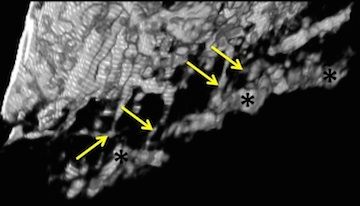

• Lamina cribrosa capillaries straighten as intraocular pressure increases

• BL Brazile, B Yang, S Waxman, P Lam, AP Voorhees, Y Hua, RT Loewen, NA Loewen, JF Rizzo, T Jakobs and IA Sigal

• Investigative Ophthalmology and Visual Science, 61(2), October 2020.